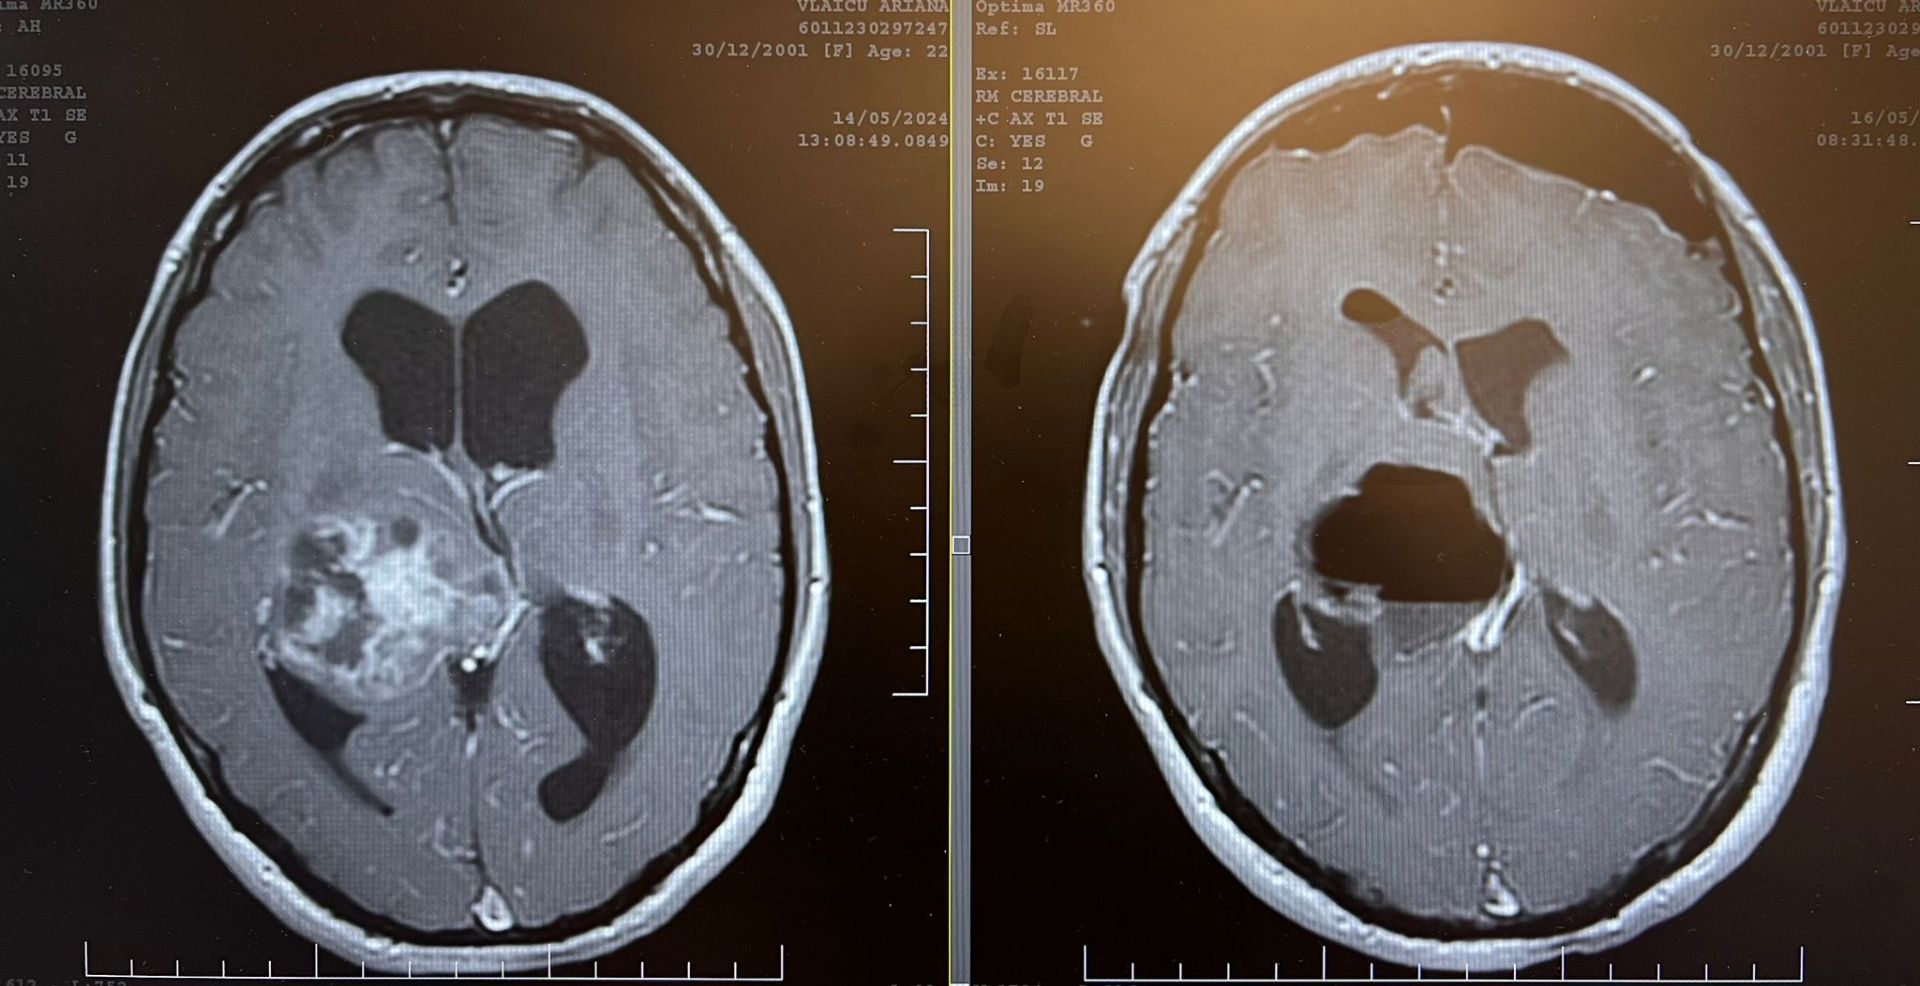

Ploieşteanca Ariana Vlaicu are nevoie urgentă de tot sprijinul oamenilor cu inimă mare. Tânăra de 22 de ani care se angajase recent la IBM, după ce terminase ASE Bucureşti în limba engleză, a fost diagnosticată cu o tumoră la creier. Tumora a fost scoasă, dar în continuare este nevoie de un tratament care, din păcate, nu se poate face decât în străinătate. Mai exact, Ariana are nevoie de un tratament cu protoni care se face într-o clinică din Marea Britanie şi care costă, pentru 3 luni, 96.000 de euro. În plus, fata mai are nevoie de cazare şi bilet de avion, pentru a sta acolo împreună cu un părinte însoţitor pe toată perioada tratamentului, ceea ce ar ridica costurile cu încă 50.000 de euro.

"Pe data de 6 mai, Ariana s-a trezit brusc cu o presiune la cap și o stare generală proastă. A fost, până în acel moment, un copil sănătos care a avut grijă de corpul ei, ducând un stil de viata sănătos. În acea zi, simțindu-se rău, am plecat la București la Spitalul "Bagdasar Arseni", de urgenţă, unde a fost diagnosticată cu tumora talamică dreapta. Starea de rău era provocată de o hidrocefalie generată de tumoră. A fost operată de urgenţă la Spitalul Monza de către dl dr. Sergiu Stoica, a fost îndepărtată tumora, însă în urma rezultatului biopsiei diagnosticul a fost de gliom grad 4. Această terapie cu protoni nu se decontează de Casa de Asigurări de Sănătate şi nici nu se face în ţară. Deocamdată am vorbit la o clinica din Anglia, dar inca suntem în căutări pentru cea mai buna variantă, pentru că mai sunt clinici in Europa care fac aceasta terapie. Am vorbit în Lyon, Franța și în Viena , Austria. Suntem în discuții și cu CAS Prahova pentru a găsi o cale să primim ajutor. Cea mai mare problemă este timpul pentru că terapia trebuie inceputa in maxim 6 săptămâni de la operatie. Ariana are nevoie de încă o şansă la viaţă şi noi, ca părinţi nu ne permitem aceste costuri. Deja am fost ajutaţi şi până acum de oameni cu suflet mare, fără de care nu am fi ajuns în acest punct. Este îngrozitor pentru noi să ştim că nu ne putem ajuta copilul şi că trebuie să cerem ajutor în jur, dar este singura şansă a Arianei la acest tratament. Le mulţumim anticipat tuturor celor care pot şi vor să ne ajute fiica! Sunteţi ultima noastră speranţă!"